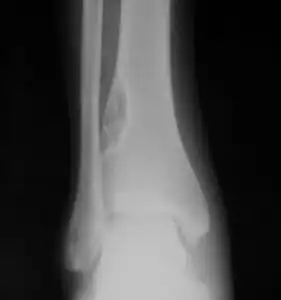

| X-ray of nonossifying fibroma of distal tibia. | |

1. a. Front view X-ray: NOF of the lower leg bone near ankle, with well-defined tumor -